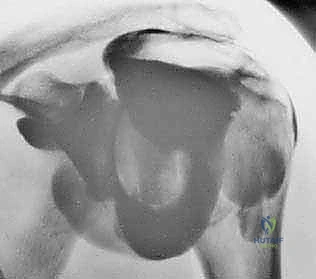

- الأشعة السينية (X-rays): لاستبعاد وجود كسور، وتقييم المسافة تحت الأخرم، ورؤية النتوءات العظمية أو التكلسات التي قد تكون سبباً في قطع الوتر.